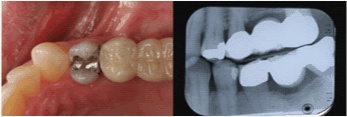

| Maxillary Right First

Molar |

4 |

89.2% |